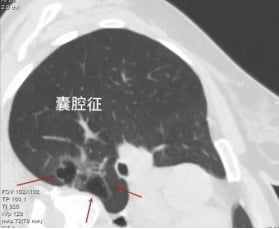

囊腔征:警惕囊腔型肺癌的伪装

囊腔征与空泡征不同,其内部空腔成分占据显著体积,远大于周围有形成分,初看易与肺大泡混淆。然而,囊腔征的壁部明显增厚,且常混杂有磨玻璃样成分,增厚不均匀,这与典型的薄壁肺大泡形成鲜明对比。因此,这并非简单的肺大泡,而是囊腔型肺癌的一种特殊表现。面对此类征象,细致入微的观察与准确的鉴别诊断至关重要,以确保及时识别潜在的恶性病变。